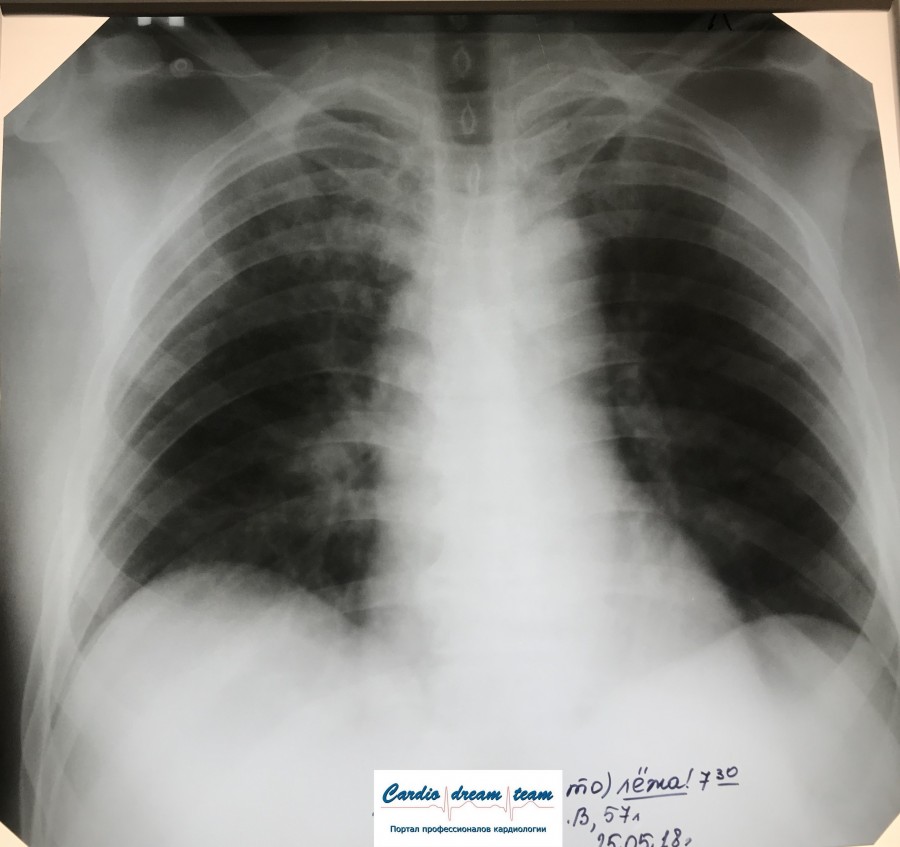

Заголовок сообщения: Синдром инфильтрации

Обсуждалось здесь https://vk.com/club84409679?w=wall-84409679_8172%2Fall

IMG_6071 %281%29.jpg

IMG_6071 %281%29.jpg [ 91.06 KiB | Просмотров: 33078 ]

IMG_6013.JPG

IMG_6013.JPG [ 248.99 KiB | Просмотров: 33078 ]